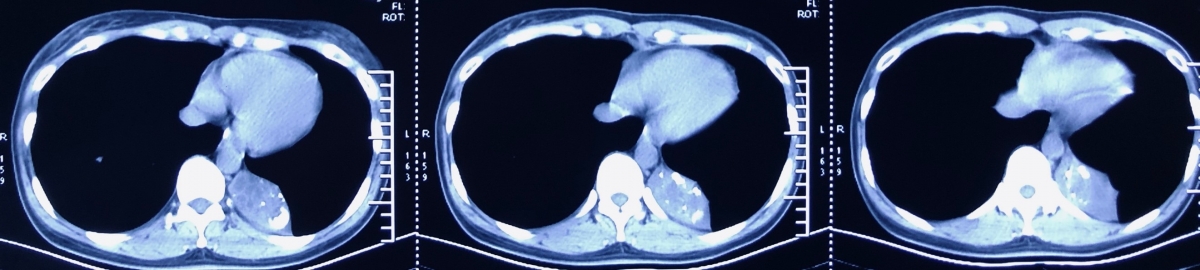

2月19日复查胸部增强CT:上叶病变同前,左肺下叶新磨玻璃影,炎症?左侧肺隔离症(左心房供血罕见)。

本例患者属叶外型,由左心房供血,较为罕见。

肺隔离症方面:肺隔离症虽非常见病但也非罕见。对于下叶后 基底段贴近横膈及心影旁的囊性肿块或边缘光滑的团块状阴影,均应考虑到本病的可能。

肺隔离症为先天性发育异常的肺疾病,其主要特点是病变由体动脉供血并与正常肺组织分离。部分患者表现为反复肺部感染、痰血或咯血。希望通过本病例让大家了解肺隔离症的影像表现,在诊断和治疗中应重视本病。